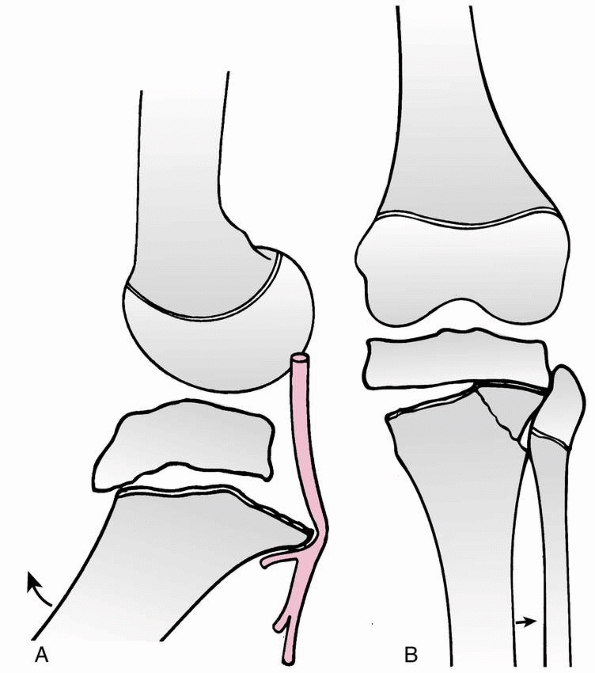

the knee joint (Fig. 23-3A). However, loading

to failure across the immature knee is more likely to lead to physeal

failure due to tensile stresses that are transmitted through the

ligaments to the adjacent physis (Fig. 23-3B).45

FIGURE 23-3 A. In a skeletally mature patient with closed physis, tensile failure usually occurs across the ligament. B.

In a skeletally immature patient with open physis, failure usually occurs across the physis. (Reprinted with permission from Skaggs DL, Flynn JF. Trauma about the knee, tibia, and foot. In Skaggs DL, Flynn JF, eds. Staying out of Trouble in Pediatric Orthopaedics. Philadelphia: Lippincott Williams & Wilkins; 2006.) |